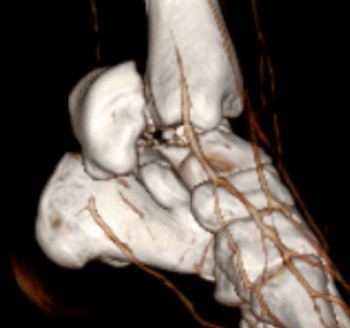

Type III: Talar body dislocated from ankle joint

Type IV: Talar head dislocated from talonavicular joint

Irreducible fractures / Extruded Talus

- anteromedial / anterolateral approach

- posteromedial approach

Posteromedial approach for open reduction of dislocated talar body

Anatomical reduction + fixation

1. Remove loose bodies from subtalar joint

2. Reduction - avoid varus and shortening medial neck

- often medial comminution